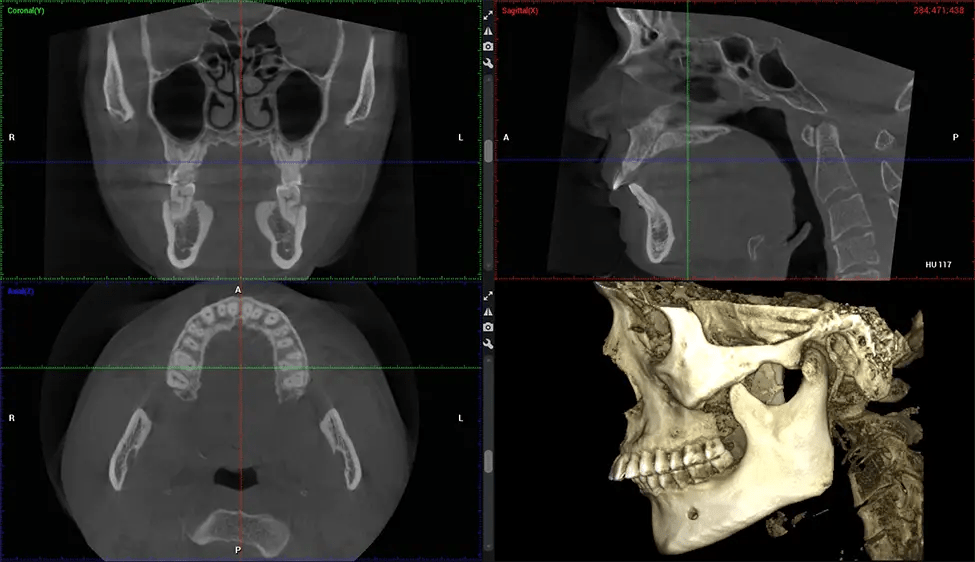

Cone Beam Computed Tomography (CBCT) is an advanced imaging technique used in dentistry and maxillofacial surgery to obtain detailed 3D images of the oral and maxillofacial structures. At Dr G Dental Studio, our CBCT scanners utilize a cone-shaped X-ray beam and a specialized detector to capture images from different angles. A computer then combines these images to create a 3D representation of the patient’s oral anatomy.

This 3D scan, called cone beam computed tomography, gives your dentist a more complete image of your oral anatomy and disease processes than a traditional X-ray. Unlike conventional X-rays, which capture a 2D image of your mouth from various angles, a 3D scan takes multiple digital X-rays for one image. It provides a complete view of your jaw, teeth, nerves, and soft tissues. This enhanced view allows dentists to detect minor issues not visible in traditional 2D scans, such as impacted wisdom teeth or bone fractures in the sinus cavity.

The patient is first positioned in the CBCT scanner, which typically consists of a rotating arm that houses the X-ray source and a detector. The patient’s head is immobilized to ensure accurate image capture. The X-ray source and detector rotate around the patient’s head, capturing various X-ray images from multiple angles. As the X-ray source rotates, it emits the cone-shaped X-ray beam towards the detector. The detector captures the X-ray images, which are then processed by the CBCT software.

After the scanning process, the captured X-ray images are processed by the CBCT software, which applies algorithms to reconstruct a detailed 3D image of the scanned area. The software compiles these individual X-ray images and creates a digital 3D representation of the patient’s anatomy. The reconstructed 3D CBCT image can be viewed and analyzed by the dentist or radiologist. This image can be manipulated, rotated, and zoomed in or out to examine specific structures and evaluate the patient’s condition.